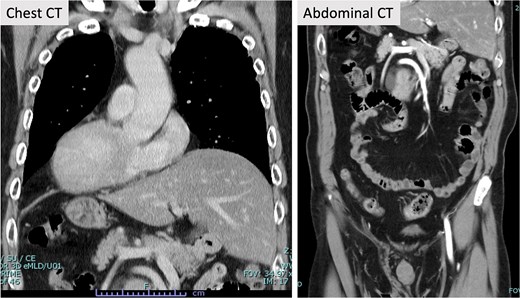

A 71-year-old male patient presented to our hospital with complaints of abnormal bowel movements. He had a history of laparoscopic cholecystectomy and had been previously diagnosed with congenital SIT (Fig. 1). Pelvic computed tomography (CT) showed a tumor in the upper rectum (Fig. 2). Colonoscopy revealed rectal stenosis due to the tumor (Fig. 2); and biopsy confirmed a diagnosis of moderately differentiated adenocarcinoma. Preoperative assessments indicated an absence of distant metastasis; therefore, robot-assisted surgery (RAS) was planned, despite the presence of SIT.

Contrast-enhanced CT. Contrast-enhanced CT revealed SIT. Other abnormalities in the blood vessels were not evident in the chest and abdomen.